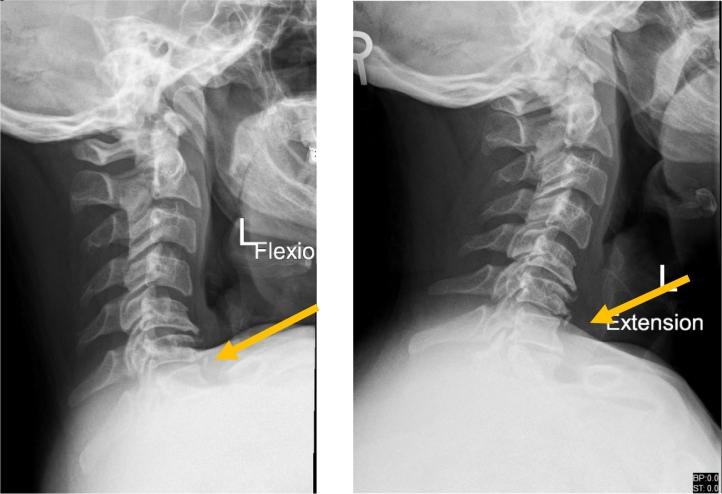

CASE PRESENTATION

A 55-year-old male presenting with neck pain, right and left arms radicular pain and numbness, and unilateral right foot drop following cervical disc prolapse. The patient presented with upper motor neuron lesion signs. MRI showed cervical disc prolapse at two levels, confirming central cause of foot drop. The patient underwent anterior cervical decompression and fusion surgery.

病例报告

一名55岁男性,因颈椎间盘突出症出现颈部疼痛、双侧手臂放射性疼痛和麻木,以及单侧右足下垂。患者表现出上运动神经元损伤体征。磁共振成像显示两个节段的颈椎间盘突出,证实了足下垂的中枢性病因。该患者接受了颈椎前路减压融合手术。